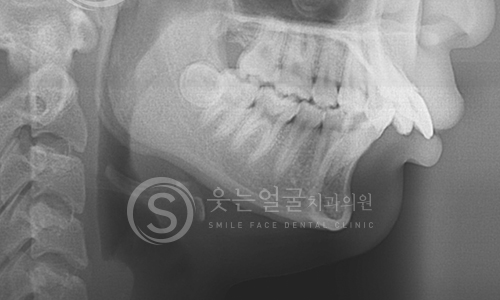

8천여건의 다양한

임플란트 수술 케이스

다년간 축적된 8,000여 건 이상의

임플란트 수술 경험을 바탕으로,

환자 개개인의 구강 구조와

상태에 최적화된 안전하고 정확한 시술을 제공합니다.